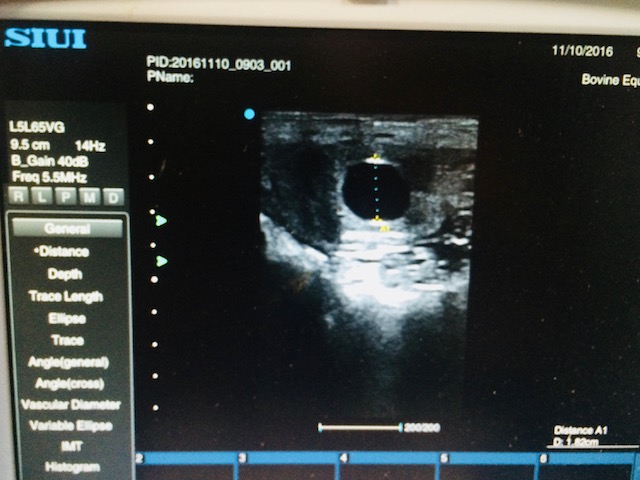

Pregnancy Diagnosis/Monitoring (Ultrasound)